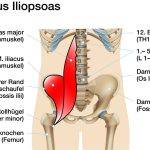

– Mạc cơ tương liên: Fascia của Cơ thắt lưng – chậu (Psoas – Iliacus)

– Thoracolumbar fascia (mạc ngực – thắt lưng): nối Thận – Cột sống – Cơ dựng sống – Cơ chéo bụng)

2- Liên kết cơ – xương – khớp: Cơ liên quan trực tiếp:

– Cơ Psoas Major, Quadratus Lumborum, cơ dựng sống

(Hình ảnh đính kèm: )